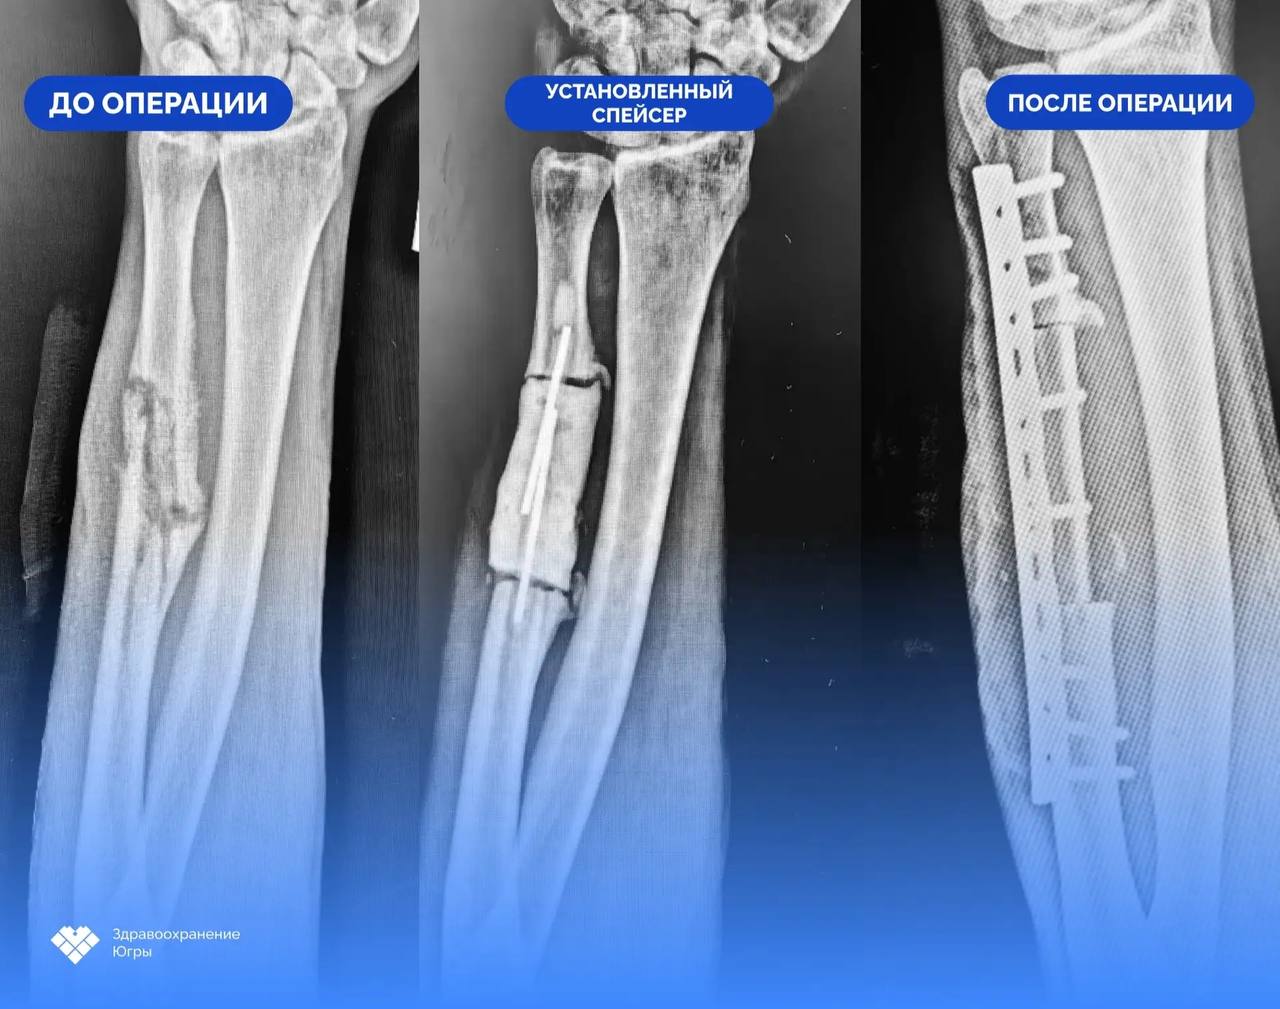

«В первую очередь выполнена санация очага инфекции, удалена нежизнеспособная костная ткань. В результате операции образовался дефект локтевой кости протяженностью 6 сантиметров. Для его замещения был установлен антибактериальный спейсер – временный цементный эндопротез с добавлением антибиотика. В течение двух месяцев он поддерживал кость, сохранял длину предплечья, а также боролся с инфекцией», – говорится в сообщении.

Спустя время пациент снова был госпитализирован для второго этапа лечения – костной пластики. Сейчас ветерану нужно будет восстанавливаться дома, в Кондинском районе. А в случае вопросов он сможет связаться со своими спасителями в Сургуте с помощью телемедицины.